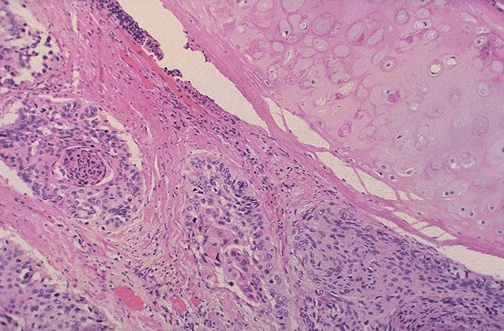

Image 7.3

The low power microscopic appearance of the mass is shown here.